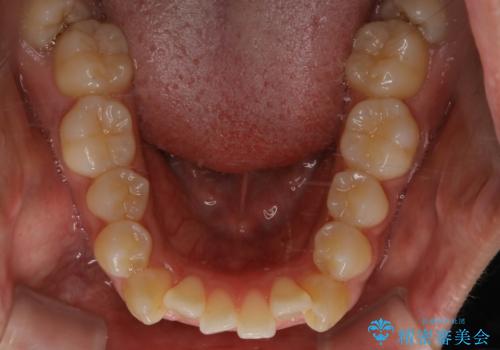

- オーディションで歯並びを指摘されたことから一念発起して矯正治療を行う事にした方です。

親知らずと、前から4番目の歯を抜歯してワイヤー装置による矯正治療を行いました。

人前に出ることが多いため、当初は目立たない装置をご希望されていましたが、歯の移動距離が大きいため効率よく歯を動かせる表側の装置での治療をお勧めしました。すれ違ってしまっていた奥歯もしっかり治すことができました。